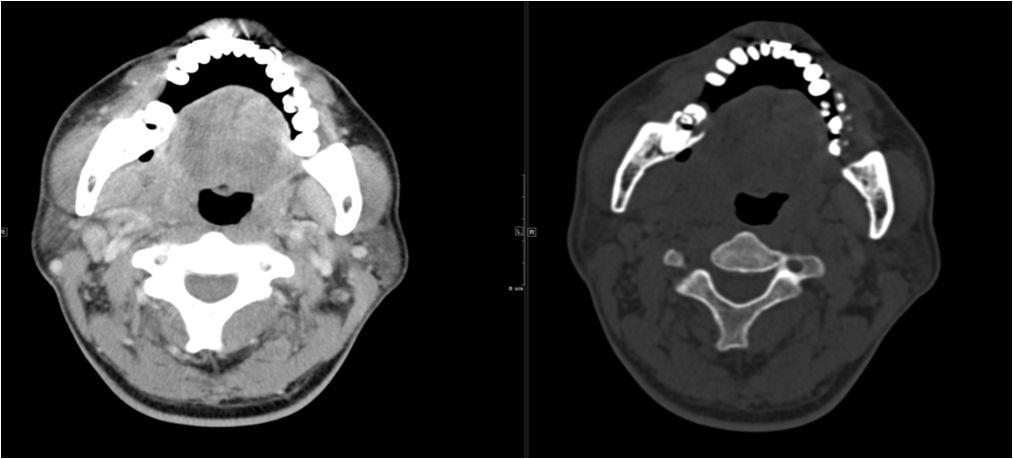

06 颌下间隙

64M,1个月前出现右下后牙钝痛伴咬合痛,自服红霉素,症状减轻。20天前发现患侧颌面及牙龈肿胀,伴有牙松动、牙周溢脓,抗炎效果不佳。约10天前曾行“脓肿切开引流”,#46、#47拔除。

骨髓炎并颌下间隙及下唇部感染。